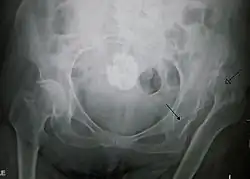

X-ray showing a joint dislocation of the left hip. | |

Typically, people with hip dislocations present with severe pain and an inability to move the affected leg.[1][4] Diagnosis is made by physical exam and plain X-rays of the hips. A CT scan is recommended following reduction to rule out complications. Complications include osteonecrosis, femoral head fractures, and posttraumatic osteoarthritis.[12][13]

An anterior-posterior (AP) X-ray of the pelvis and a cross-table lateral X-ray[24] of the effected hip are ordered for diagnosis.[4][5][16] The size of the head of the femur is then compared across both sides of the pelvis. The affected femoral head will appear larger if the dislocation is anterior, and smaller if posterior.[7] A CT scan may also be ordered to clarify the fracture pattern.[20]